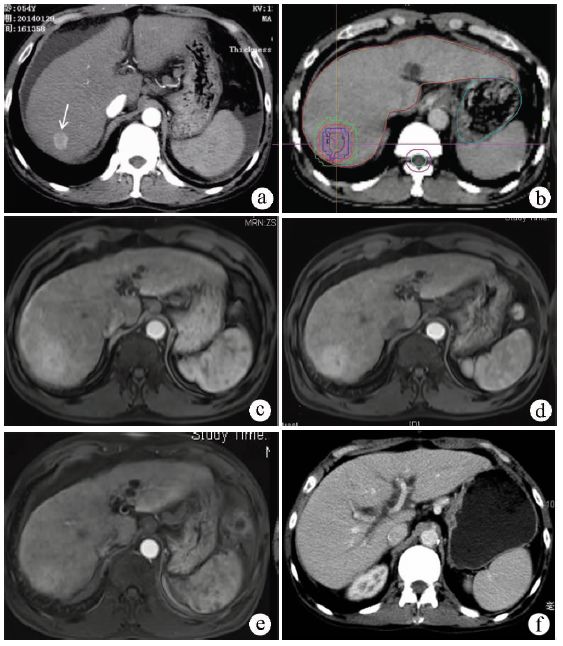

研究[11]报道,379例患者接受肝移植的移植前桥接治疗,其中36例接受SBRT,99例接受介入栓塞化疗,244例接受射频消融。最终有312例患者获得肝移植,SBRT组30例,介入栓塞化疗79例,射频消融203例,3组获得肝移植的概率相似。1、3、5年生存率分别为:SBRT组83%、61%和61%,介入栓塞化疗组86%、61%和56%,射频消融组86%、72%和61%,3组间无明显差异(P=0.4)。SBRT作为肝细胞癌移植前的桥接治疗,和介入栓塞、射频消融一样安全有效。对伴有腹水、凝血酶原时间延长的肝细胞癌患者的移植前桥接治疗,相比介入栓塞、射频消融,SBRT更有优势。病例4为肝功能为Child-Pugh C 级的小肝癌患者,在22个月的等待肝源期间,接受SBRT,最终获得肝源,成功移植(图4)。

注:a,放疗前增强CT,右后叶病灶2 cm,箭头所示,动脉期强化,中等量腹水;b,CT 和MRI融合确定靶区,制定SBRT计划,肿瘤50 Gy/5次;c~e,分别为放疗后2、5、9个月随访的MRI,肿瘤消失,放疗区域(瘤床)充血,系放疗后改变,少量腹水;f,放疗后22个月等到肝源,接受肝移植,移植后1年随访CT。

图4 肝细胞癌肝移植前的桥接放疗